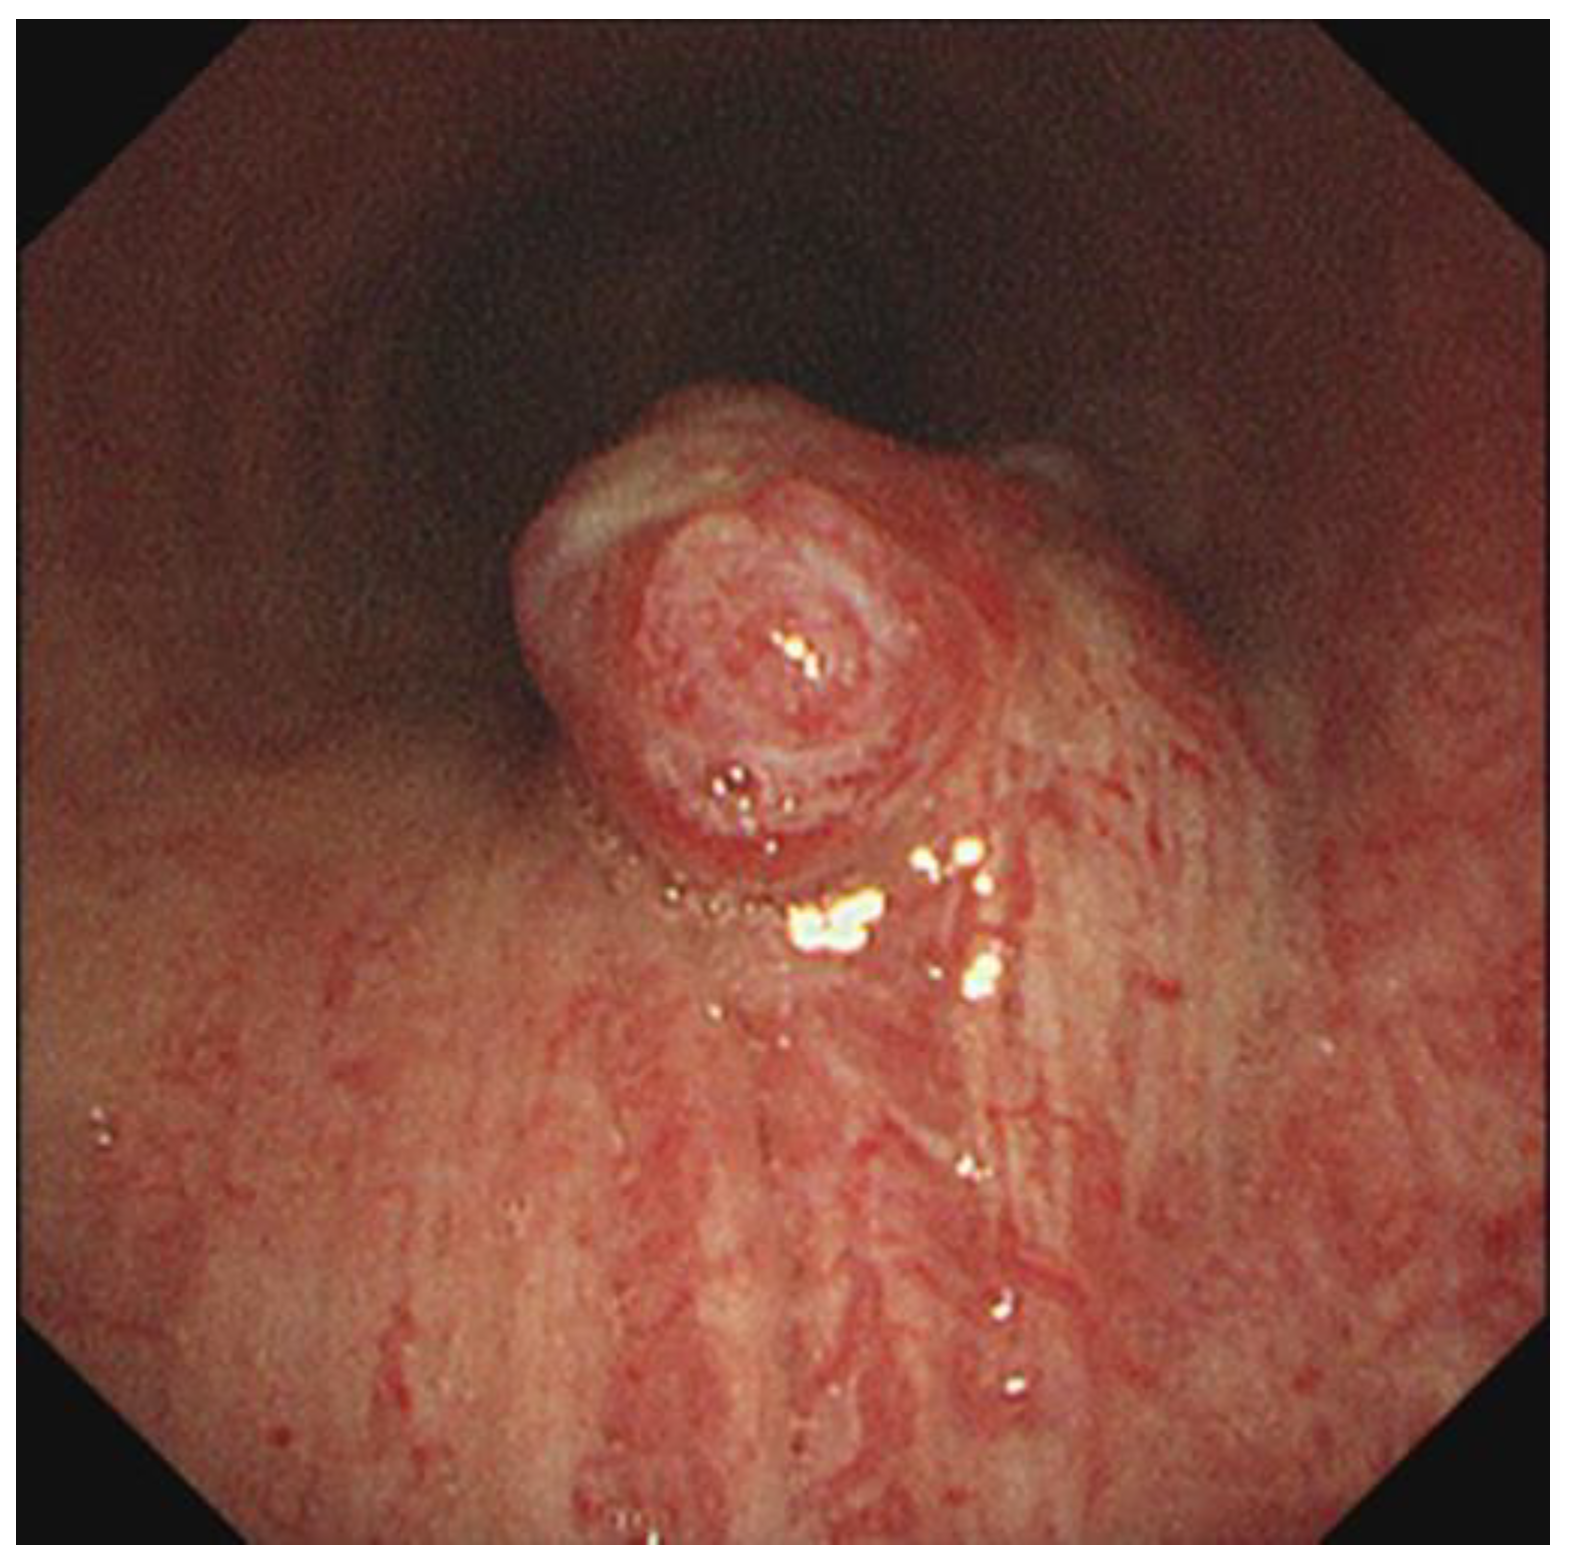

Tracheal Glomus Tumor: A Case Report with CT Imaging Features

2. Case Description